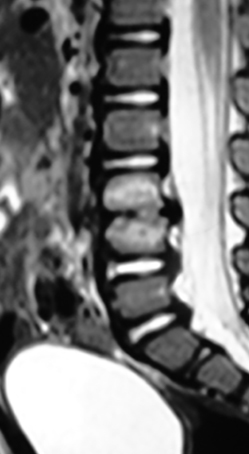

Infección

Las causas infecciosas se deben considerar en la evaluación de un niño con dolor de espalda. La discitis aparecen en dos picos de edad, en niños menores de 5 años y en niños de 10 a 14 años (36). La presentación puede ser tan variada que puede incluir además de dolor de espalda, dolor abdominal, cojera o rechazo al caminar. El examen físico mostrará límite al movimiento de la espalda y dolor a la palpación localizada. Radiográficamente los hallazgos se observan atrasados con relación a los hallazgos físicos. De verse algún hallazgo, será la irregularidad de los bordes vertebrales, usualmente entre L2-L3 o L3-L4. El mejor estudio es la cintigrafía ósea para localizar la lesión y la RM para definir la extensión especialmente si hay un absceso epidural, que requiera drenaje quirúrgico inmediato (Figura 5). Los laboratorios mostrarán una elevación de la velocidad de sedimentación, mientras que el nivel de glóbulos blancos solo se elevará en un 10% - 40% de los casos. Por lo tanto, el nivel de los glóbulos blancos no es confiable (36).

El tratamiento debe ser descanso, abrazadera para inmovilizar la columna vertebral y antibióticos intravenosos. Empíricamente el antibiótico debe ser encaminado a cubrir se estafilococo aureus, que es el organismo más común. El tratamiento quirúrgico se reserva a los casos en que el paciente no mejore en varios días con el descanso y antibióticos o cuando se ha documentado la presencia de un absceso epidural (37).Osteomielitis vertebral